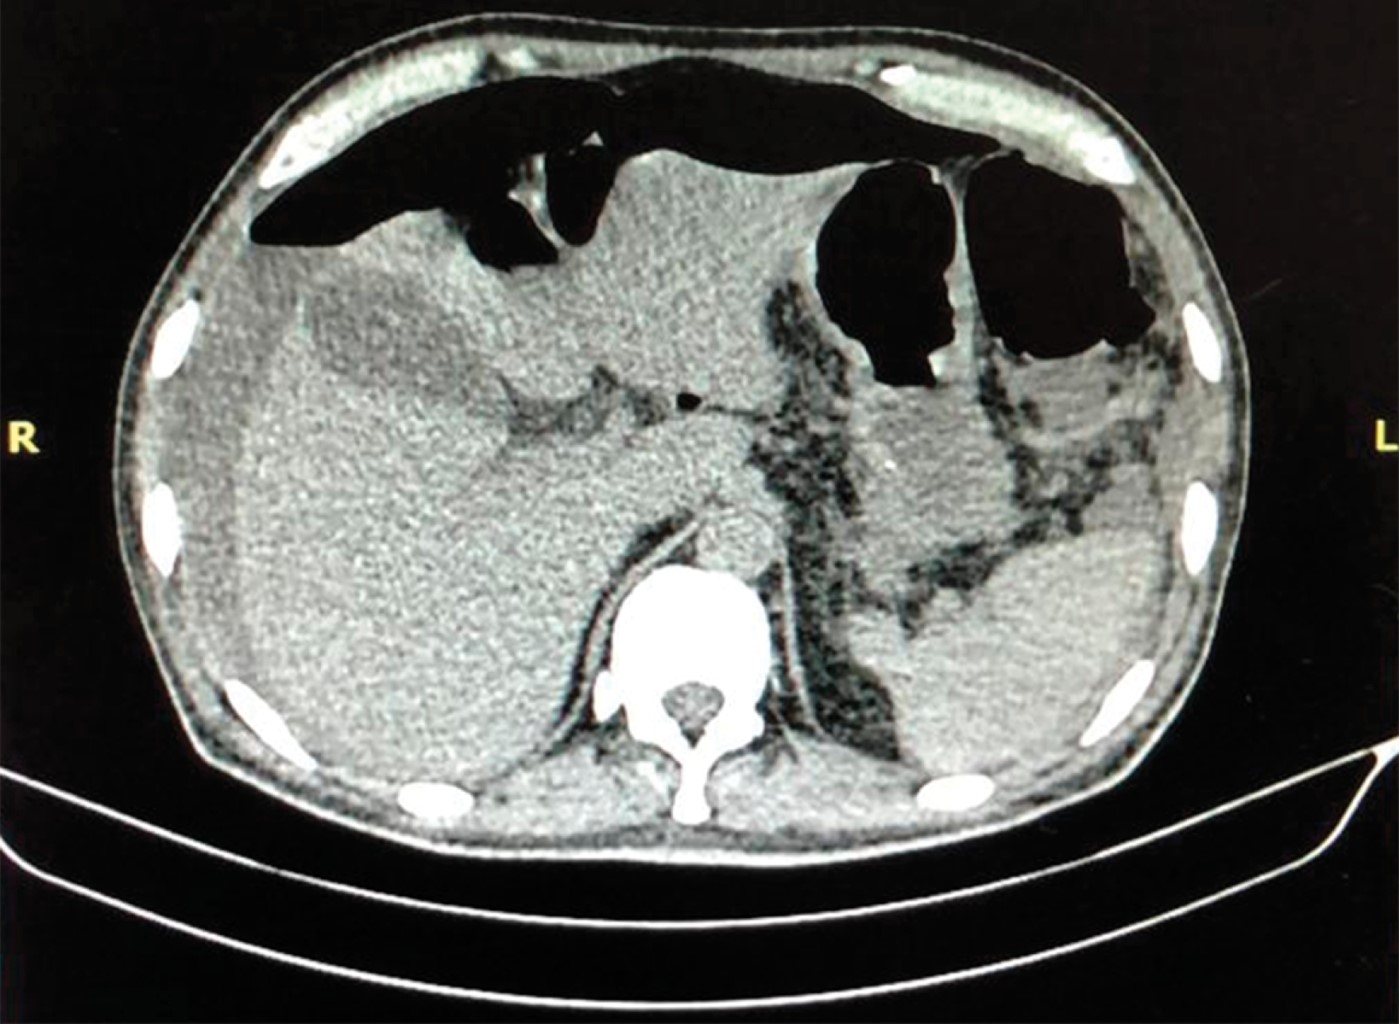

Se presenta el caso de un masculino de 62 años de edad, originario y residente de la Ciudad de México, con antecedente de hipotiroidismo y artropatía no especificada en tratamiento con esteroides y antiinflamatorios no esteroideos desde hace cinco años. Se presentó al servicio de urgencias con dolor abdominal de una semana de evolución, que inició de manera inespecífica en epigastrio y que posteriormente se volvió generalizado, opresivo y gradualmente progresivo en intensidad hasta volverse incapacitante. Negó algún factor desencadenante específico, refirió episodios de melena en días previos. Como parte del abordaje se realizaron estudios de laboratorio, se documentó la presencia de leucocitosis a expensas de monocitos, y de gabinete con una tomografía abdominal en la que se observó aire y líquido libre en cavidad abdominopélvica (Figura 1). Clínicamente con datos de irritación peritoneal y choque séptico de origen abdominal.

Figura 1